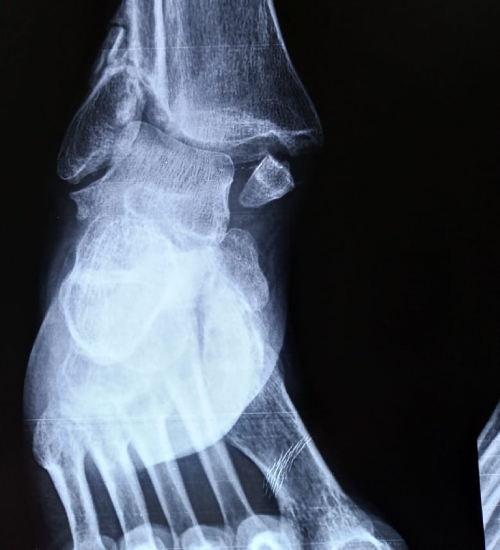

• Fracturas e inestabilidad de tobillo.

• Fracturas complejas de clavícula, hombro, codo, muñeca, cadera, rodilla, tobillo y pie.